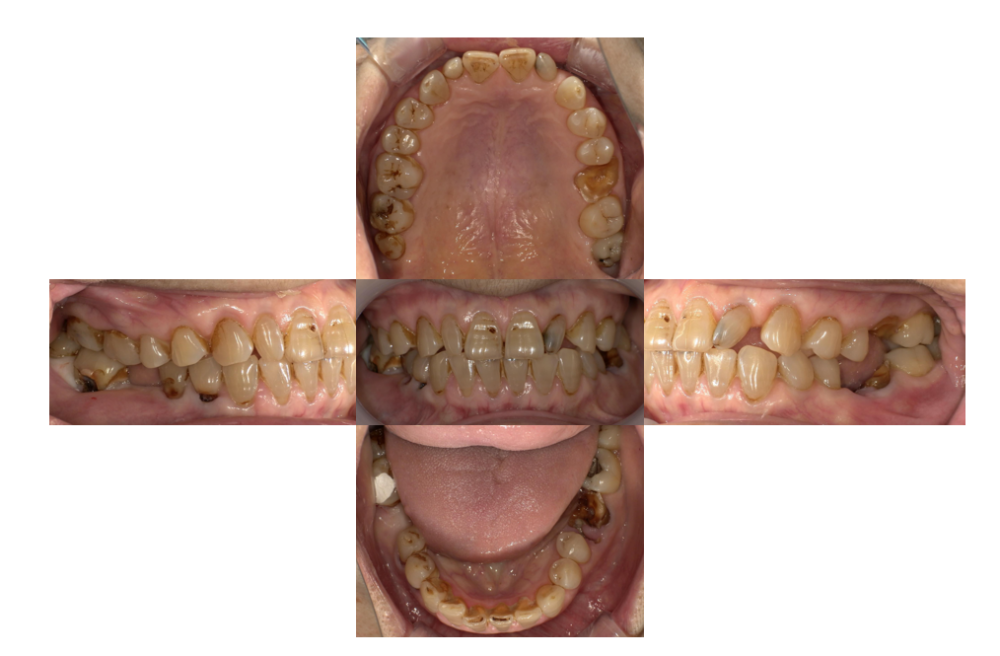

症例3

治療前

治療後

| 主訴 | 歯を入れたい |

「右下」67欠損 |

| 治療内容 | 右下67左下6インプラント、左上⑤6⑦ジルコニアブリッジ |

| 年齢・性別 |

68歳 男性 |

| 治療期間 |

8ヶ月 |

| 治療費用 | ①左上⑤6⑦ジルコニアブリッジ¥264000 ②右下67左下6インプラント(3本) 診査診断¥22000+一次手術(京セラ)¥825000+左下6GBR¥110000+上部構造¥429000 総額¥1386000 |

| リスク・副作用 | インプラント周囲炎、インプラント上部構造の緩み |